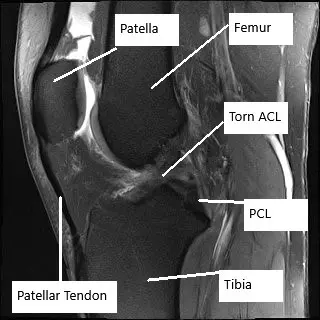

MRI of the knee in the sagittal section showing torn ACL.

MRI of the right knee revealed a full-thickness ACL tear with a bone contusion pattern indicative of a recent anterior tibial translation. The ACL tear has now progressed to full-thickness and is worse compared to the prior study. Tearing of the medial and lateral meniscus, progressive in severity since the prior study.